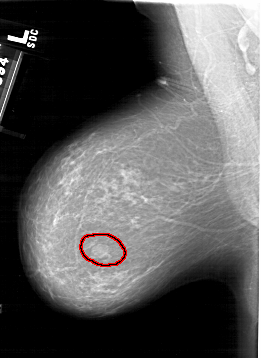

A_1498_1.LEFT_CC

FILE: A_1498_1.LEFT_CC.OVERLAY

TOTAL_ABNORMALITIES 1

ABNORMALITY 1

LESION_TYPE MASS SHAPE OVAL MARGINS OBSCURED

ASSESSMENT 4

SUBTLETY 4

PATHOLOGY BENIGN

TOTAL_OUTLINES 1

BOUNDARY